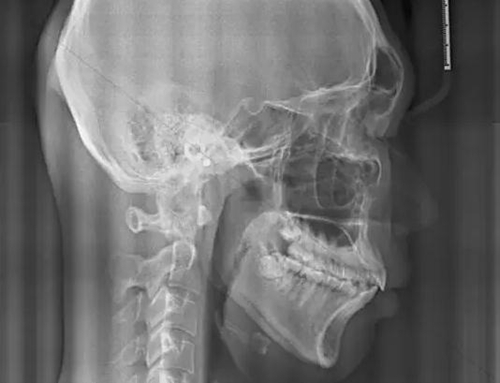

賀老師提到兒童青少年最常見的兩種阻塞呼吸道的問題即腺樣體肥大和扁桃體肥大。首先我們通過頭顱側(cè)位片來了解一下這兩個腺體在x線片上的位置。

以下兩張標(biāo)注的是肥大的腺樣體及其位置